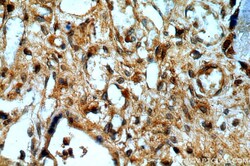

- Invitrogen Antibodies (provider)

- Main image

- Experimental details

- Immunohistochemistry of paraffin-embedded human placenta using 14412-1-AP (PEG10 antibody) at dilution of 1:100 (under 40x lens).